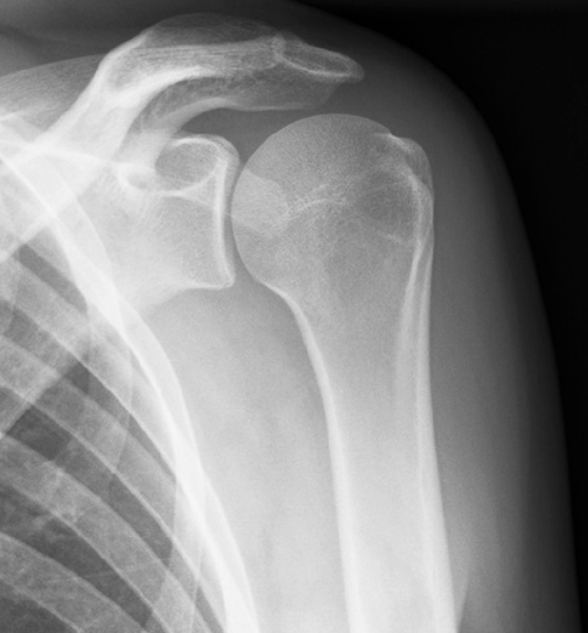

두 번째, 신체 진단에서 예상되는 진단을 확인하기 위해 가장 기본 검사인 엑스레이를 촬영합니다. 동결견은 X선상 이상소견이 발견되지 않지만 류마티스 관절염 또는 골성관절염, 석회성건초염 등 어깨의 다른 질환과 감별진단이 가능합니다.